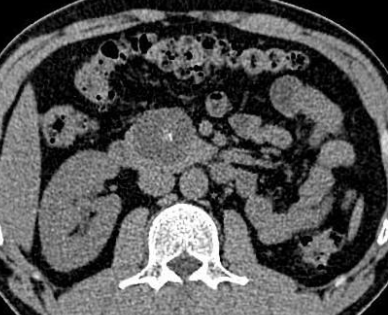

Cystadénome Mucineux

- Bénin mais risque de transformation Cystadénocarcinome Mucineux (non distinguable)

- Masse kystique plutot grande >2cm

- Queue du pancreas ++

- Plus il y a de mucine plus elle est hyperT1

- Capsule pouvant être épaisse

- Calcifications plutot périphériques

- Mother Lesion (98% femmes d’age moyen!)